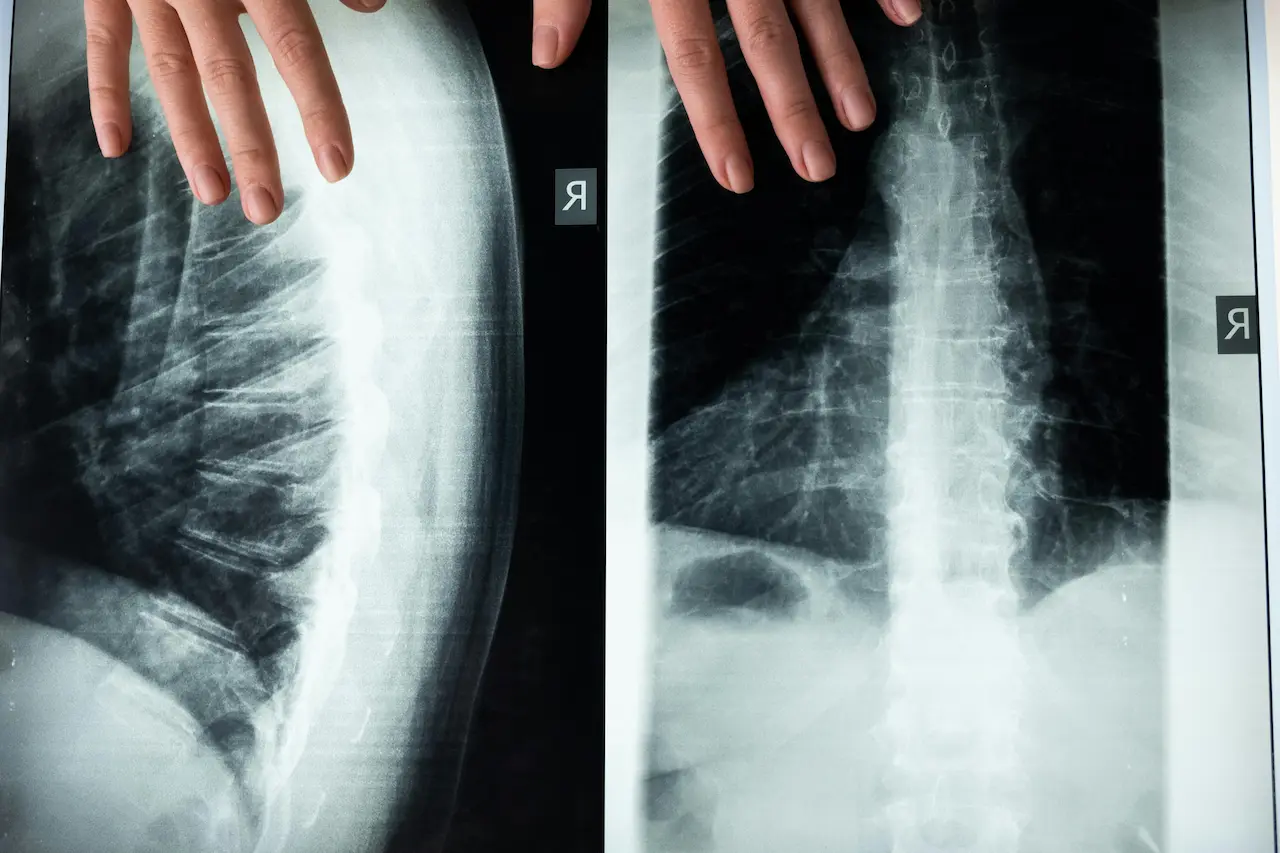

Chiropractic care involves clinical assessment and management of musculoskeletal conditions, with a particular focus on the spine and how it relates to movement and symptoms such as pain, stiffness, or “referred” sensations (for example, pain that spreads into an arm or leg).

A chiropractic assessment generally aims to clarify what is most likely contributing to symptoms, what can be modified, and what is safest and most appropriate for the individual. This typically includes history-taking, physical examination, and screening for issues that may need medical referral.

Chiropractic care often focuses on the spine, but assessment may consider related joints and movement patterns (for example, hips and thoracic spine contributing to low back symptoms). The exact focus depends on the person’s symptoms and goals.